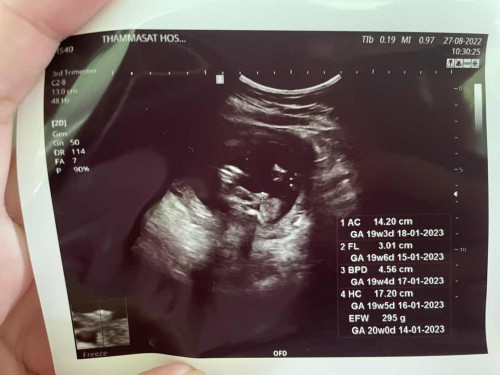

คุณหมอบอกลูกสาวแน่ๆ อิพ่ออิแม่ดีใจมากกลัวจู๋จะโผล่ แม่ๆช่วยดูหน่อยนะคะว่า ช หรือ ญ

ไม่100%เลยค่ะว่าเพศไหน รอลุ้นอีกรอบหน้านะคะ